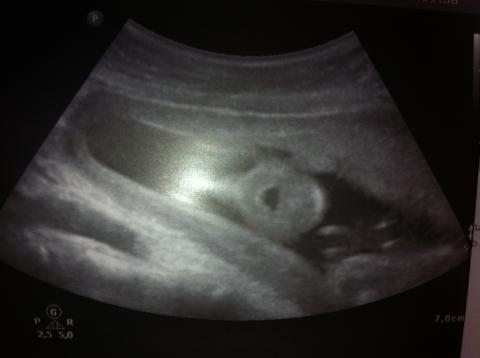

Dobrý den, je mi 20let, 20+6tt, byla jsem dnes v rámci genetického vyš. na ultrazvuku. Nejprve paní doktorka chválila, říkala jak je vše v normě a jak má být, ale potom si všimla, že miminko má po celou dobu vyšetření otevřenou pusinku. Prý to není normální a jsme objednáni za týden na další kontrolu. Nikde jsem nemohla najít co by to mohlo znamenat, nebo z jakého důvodu? Můžete mi poradit co by mohlo být špatně? Testy na DS vyšly negativní. Přikládám foto. Děkuji za Váš názor.

Miminko bežne otvára a zatvára ústočká, ale nestretla som sa za 11 rokov praxe, že by počas celého UZ vyšetrenia malo len otvorenú pusinku a nehýbal s ňou.